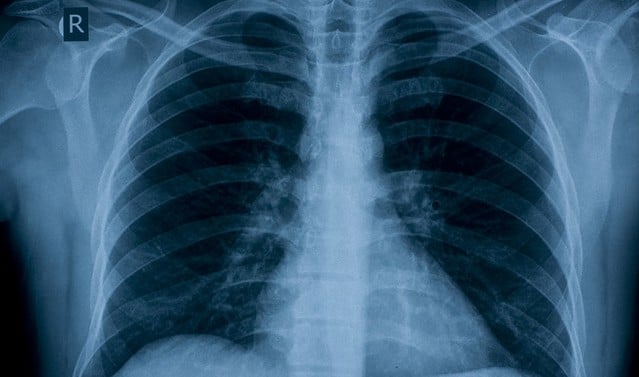

擁有健康的牙齒與牙齦有助減低患上肺炎及慢性阻塞性肺病等肺部疾病的風險。

口腔中的細菌不單停留在口腔內,還有可能不經意透過唾液飛沫將它們吸入肺部,對於肺部健康的人問題不大,但患有肺部疾病或易受感染的人可能最終會感染肺炎或慢性阻塞性肺病。

擁有良好的牙齒衛生可以保護自己免受肺炎感染。研究顯示,特別對於住在療養院或醫院中的老年人來說,口腔疾病是其中一個導致肺炎最常見的原因。一項研究估計擁有良好的口腔健康可以預防十分一在療養院因肺炎死亡的可能。這也適用於其他人群,一項對超過26,000美國人的分析發現,良好的口腔健康和定期檢查牙齒可以減低患上肺炎的風險。

慢性阻塞性肺病 (COPD) 是一個終身的肺部疾病並與較差的口腔衛生有關,它正影響全球2.5億人口。慢性阻塞性肺病不僅令患者呼吸困難,還會令患者有更高機會患上其他健康問題如心臟病和肺癌。